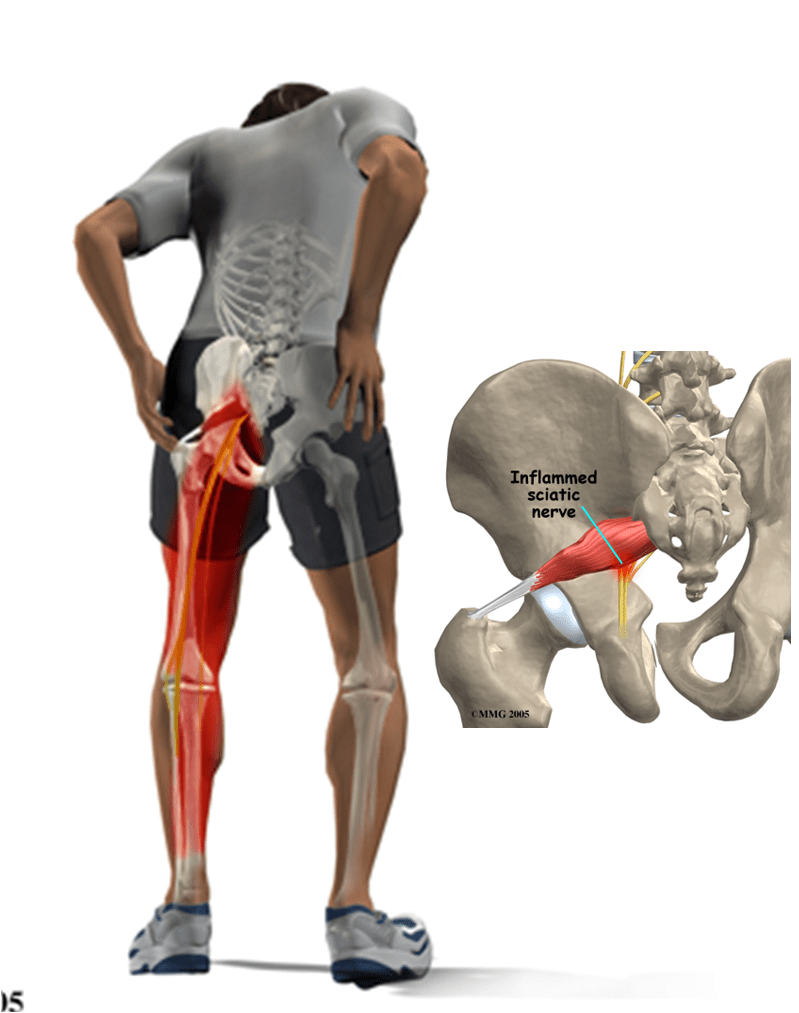

Анатомия мышц: Пириформис